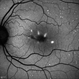

- macula serpiginous choroidopathy, Optos, fundus autofluorescence (FAF), macula lesion, ultra-wide field imaging, fundus photograph

- Optos ultra wide field auto fluorescent image of 20-year-old female presenting with serpiginous choroidal atrophy. Patient was unaware of vision loss OD, until accidentally covering OS and noticing the change. Acuity of 20/200 OD and 20/15 OS at time of imaging.